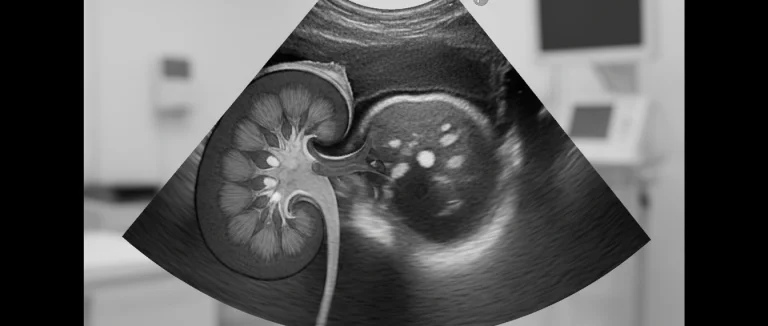

Для подтверждения диагноза врач обычно назначает общий и посевной анализ мочи, а при подозрении на поражение почек – УЗИ брюшной полости или КТ. В некоторых случаях применяется спектральный анализ мочи (мочевой скрининг) для быстрого определения наличия бактерий.

| УЗИ почек | Оценка наличия гидронефроза, абсцесса | Подозрение на почечную инфекцию |

В Лив Хоспитал вам предоставят полный спектр диагностических процедур, включая УЗИ, КТ и лабораторные исследования, а также индивидуально подобранный план лечения под контролем опытных урологов и нефрологов. Больницы группы аккредитованы JCI, что гарантирует высокий уровень качества медицинской помощи и соблюдение международных стандартов.

Для подтверждения инфекции врач назначает общий анализ мочи (выявление лейкоцитов, бактерий, крови), посев мочи (определение возбудителя и чувствительности к антибиотикам). При подозрении на поражение почек проводят ультразвуковое исследование (УЗИ) для оценки гидронефроза или абсцесса, а в сложных случаях – компьютерную томографию (КТ). Иногда используют спектральный анализ мочи для быстрой диагностики.